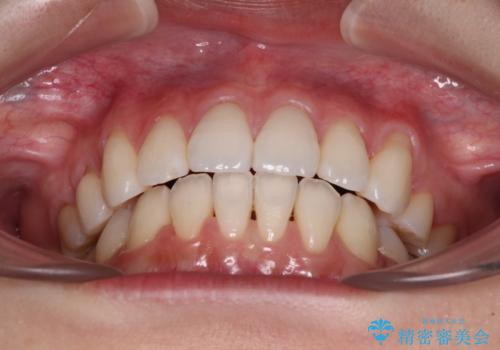

- 八重歯と口元の突出感を気にして来院された患者様です。

歯列が前方に突出しており、上下の正中がズレていたため、左側は上下第一小臼歯を、右側は上下第二小臼歯を抜去し、ワイヤー装置による矯正治療を行うこととしました。

当初はインビザラインによる矯正治療をご希望でしたが、正中を合わせたいことや、口元の突出感を改善したいことから、ワイヤー矯正を強く推奨しました。

治療期間は2年に満たず、スッキリとした口元に仕上がりました。